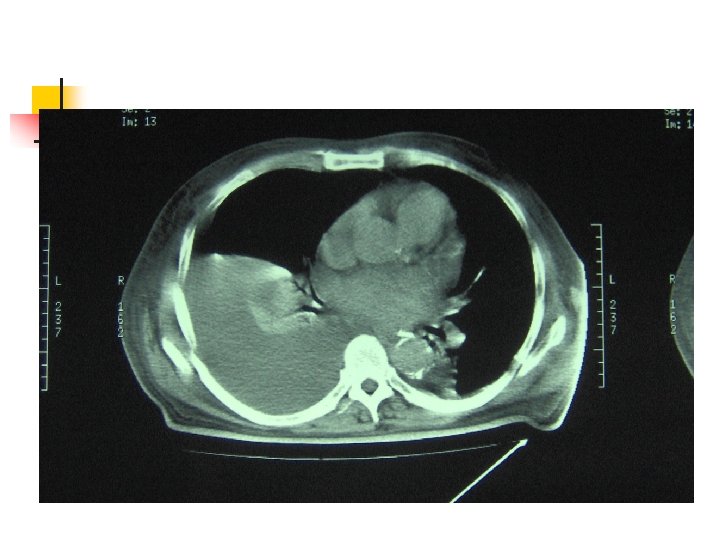

Aproximación diagnóstica: TAC Siempre TAC contraste n n Evaluar parénquima vecino Evaluación del mediastino. Desplazamiento contralateral Evaluación de DP tabicado Angio. TC Porcel JM, Light RW. Am Fam Physician 2006: 73: 1211

Broncofibroscopía Sospecha de neoplasia n Masa pulmonar en TAC o RX tórax n Derrame pleural masivo n Hemoptisis n Desplazamiento del mediastino hacia el lado del derrame Antunes G. Thorax 2003; 58: 29